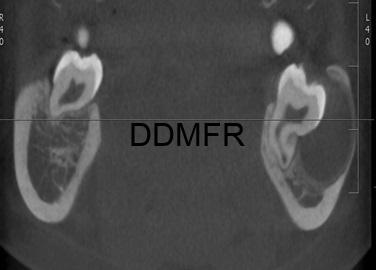

– Ακτινογραφικά απεικονίζεται σαν μονόχωρη διαύγαση, περιγεγραμμένη, με σαφή όρια, που περιβάλλει τμήμα της μύλης και των ριζών των ημιεγκλείστων γομφίων της κάτω γνάθου.

– Στην Υπολογιστική Τομογραφία συχνά παρατηρείται γλωσσική παρεκτόπιση των ριζών του δοντιού και στοιχεία αντιδραστικής περιοστίτιδας, κυρίως παρειακά.